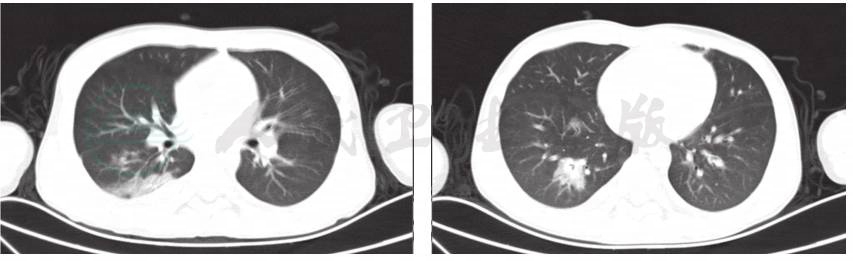

辅助检查:血常规:白细胞计数10.3×109/L,中性粒细胞百分比84.2%,淋巴细胞百分比8.3%,红细胞计数4.36×1012/L,血红蛋白126g/L,血小板 150×1012/L;CRP 87.2mg/L;降钙素原7.22ng/ml;DIC基本正常;肝功能正常;痰培养未见细菌真菌生长;血培养未见细菌生长;6天前肺CT显示双肺多发渗出,以右肺下叶为主伴有实变,双侧胸腔积液(图1);入院前1天肺CT显示双肺下叶实变范围较前增大。双侧胸腔、右侧叶间积液较前减少(图2)。

图1 入院前6天肺CT